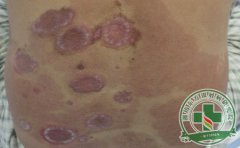

牛皮癣是一种常见的皮肤病,临床上一般有四种分型,其治疗有一定...[详细]